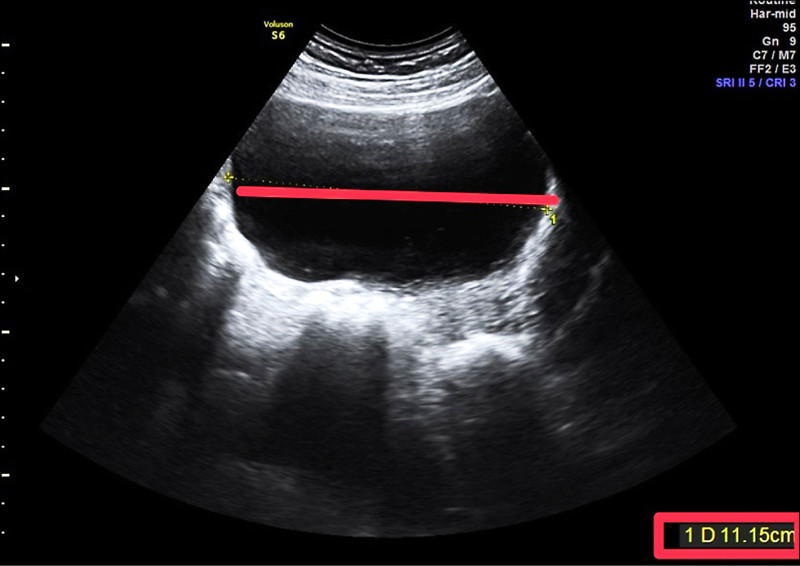

林新旺指出,患者出國前健檢發現左側卵巢囊腫,從超音波影像明顯可見,左側卵巢有1顆11×10公分的巨大卵巢囊腫,由於囊腫過大,建議以腹腔鏡摘除囊腫,約定在返台後手術。